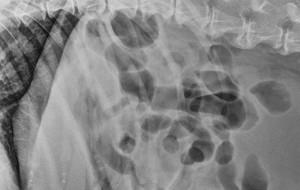

Today's case is a 10 year old FN Rottweiler with anorexia, diarrhea, and weight loss. Access all images and case information. Case originally posted on June 4, 2007 … [Read more...]